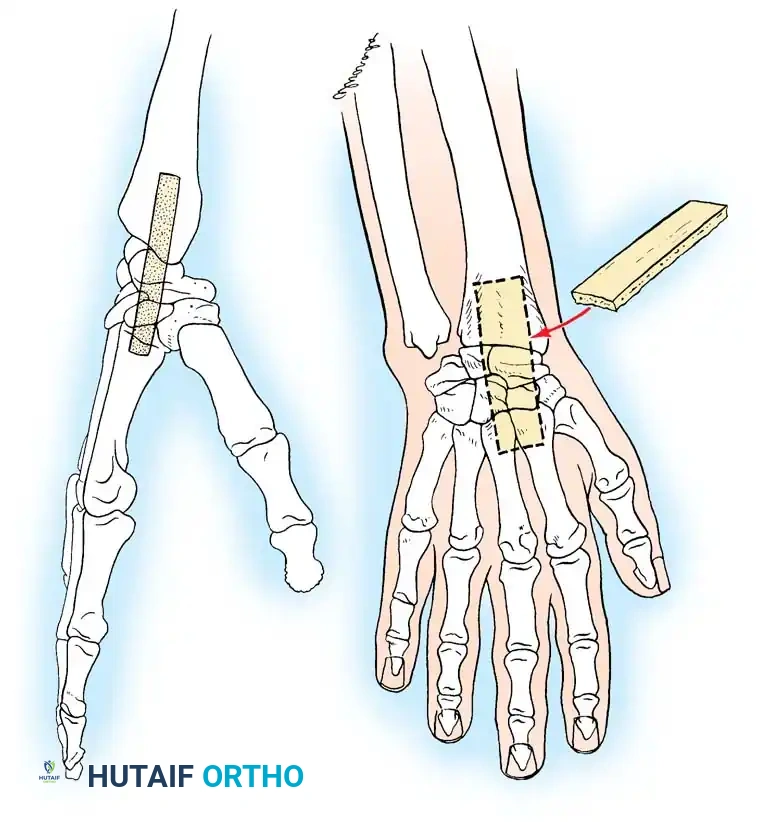

Fig. 4-23: Haddad and Riordan arthrodesis of the wrist. (A) Radial view showing the slot cut into the distal radius, carpal bones, and the bases of the second and third metacarpals. (B) Dorsal view showing the shape of the graft and its final position (broken line) within the slot.

Step-by-Step Surgical Procedure

- Incision: Make a J-shaped skin incision beginning 2.5 to 4 cm proximal to the radial styloid on the midlateral aspect of the forearm. Extend it distally across the styloid, curving dorsally to terminate at the base of the second metacarpal.

- Nerve Mobilization: Carefully identify, mobilize, and retract the superficial branch of the radial nerve (usually in a palmar direction).

- Compartment Release: Identify the interval between the first dorsal compartment (APL, EPB) and the second dorsal compartment (ECRL, ECRB). Incise the dorsal carpal ligament in this interval, leaving it attached to the volar aspect of the radius.

- Subperiosteal Dissection: Subperiosteally elevate and retract the abductor pollicis longus, extensor pollicis brevis, and the wrist/finger extensors to expose the radial aspect of the radiocarpal joint.

- Tendon Management: Divide the extensor carpi radialis longus (ECRL) tendon just proximal to its insertion at the base of the second metacarpal. Leave a sufficient distal stump to allow for robust repair during closure.

- Capsulectomy: Excise the capsule overlying the radiocarpal, intercarpal, and second carpometacarpal joints.

- Vascular Control: Identify the dorsal branch of the radial artery. Ligate and divide it to allow full access to the radial column.

- Slot Preparation: Using an oscillating saw and osteotomes, create a precise, continuous longitudinal slot through the radial styloid, across the scaphoid and trapezoid, and into the base of the second (and optionally third) metacarpal.

- Graft Harvesting and Insertion: Harvest a matching cortical strut graft (typically from the inner table of the iliac crest or proximal tibia). Impact the graft firmly into the prepared slot. The graft acts as both a biologic osteogenic scaffold and a mechanical strut.

- Fixation: Supplement the strut graft with crossed Steinmann pins or screws to provide rotational stability. Repair the ECRL tendon and close the wound in layers.